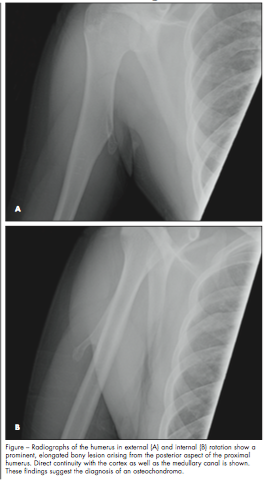

A radiograph of the affected area revealed a prominent, elongated bony lesion arising from the

posterior aspect of the proximal humerus (Figure). The radiologist recommended CT to confirm the suspected diagnosis of osteochondroma. A CT scan of the humerus delineated the lesion as a 4-cm pedunculated exostosis along the posteromedial aspect of the proximal diaphysis that extended into the medial aspect of the triceps muscle, consistent with an osteochondroma.

The lesions can be sessile or pedunculated, frequently involve the metaphyseal region of the bone (specifically the distal metaphysis of the femur or the proximal metaphysis of the tibia, fibula, or humerus), and point away from the adjacent joint.2,3 Solitary osteochondromas, such as the one in this patient, are composed of both cortical and medullary bone with a cartilage cap. A definitive diagnosis of osteochondroma can be established when it demonstrates direct continuity with the cortex as well as the medullary canal (see Figure). The osteochondroma in this case is a slightly atypical presentation in that it is more diaphyseal than is commonly seen.